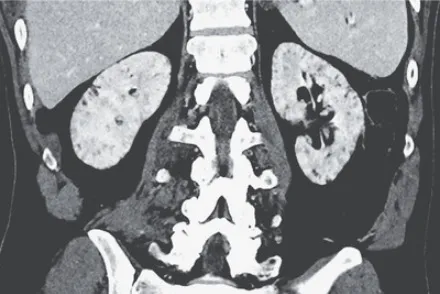

Paciente dislipidêmica, 47 anos, tomando suplemento "natural" para colesterol. Nenhuma queixa renal — até a creatinina chegar em 4.26. O agente não era uma droga controlada. Era arroz vermelho fermentado. E o rim foi o alvo.